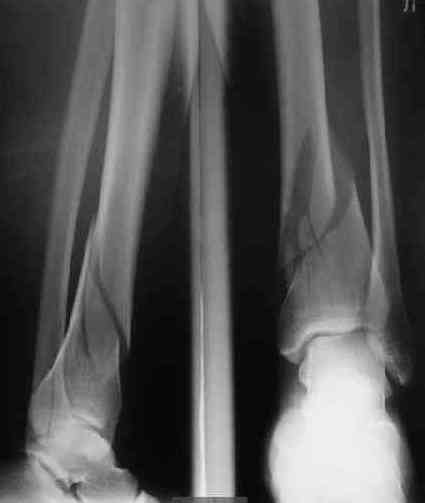

В приложении пример лечения аналогичного повреждения (плюс задний край).